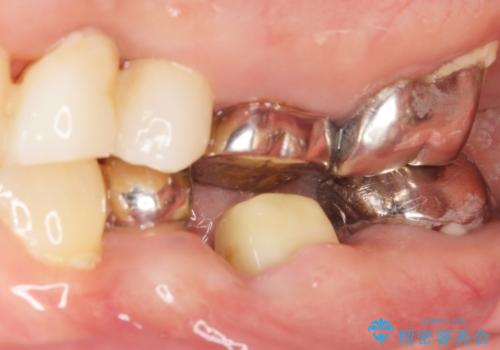

精査したところ奥歯(左下6)が破折しており、保存不可能と診断されました。

保存不可能な奥歯(左下6)を抜歯し、機能していない親知らず(左下8)の移植を行いました。

移植後、生着を待って根管治療及び補綴修復を行いました。

機能していない親知らずを用いて咬合を回復することができ、喜んで頂けました。

被せ物の種類:メタルボンドクラウン エコノミー